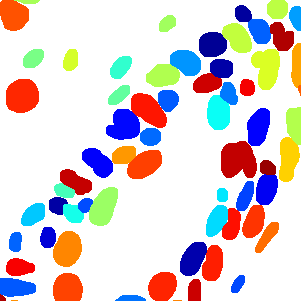

As an essential part of digital pathology, histopathology image analysis is playing increasingly important role in cancer diagnosis, which can provide direct and reliable evidence to diagnose the grade and type of cancer. This paper deals with nuclei segmentation, an important step in histopathological image analysis. The purpose of nuclei semgentation is not only counting the number of nuclei but also obtaining the detailed information of each nucleus. So unlike nuclei detection, here the outputs are the contour of each nucleus instead of only the position of their central points. Hence we can exactly extract each nucleus from the image and make it available for further analysis. For example, the features of the individual nucleus and the distribution of nuclei clusters can be used to grade and classify status of breast cancers [3, 4]. Because of appearance variation such as color, shape, and texture, nuclei segmentation from histopathological images could be very challenging, as illustrated in Fig.1, in which it is very challenging even for human to recognize and segment all nuclei within the images. Fig.1(a) and Fig.1(b) illustrate two histopathological images from different organs. Fig.1(c) and Fig.1(d) are two histopathological images from same organ but have different cancer grade.